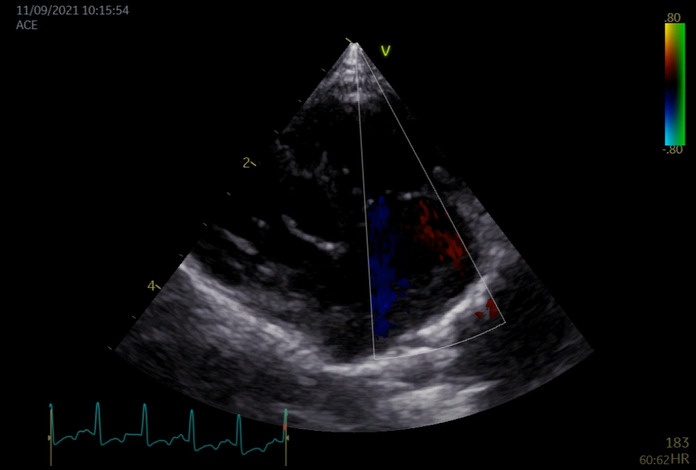

図3C 心原性肺水腫の猫における肺超音波画像

雑種猫、8歳5カ月齢、去勢雄、体重4.68kg。心疾患の管理中であったが、3日ほど投薬できておらず、かかりつけ医より紹介来院した。肺水腫によりB-lineの増加(white lung)が認められた。

特集 悩ましい猫の肺炎 vs. 肺水腫 vs. 肺腫瘍(塗木貴臣先生)図3Ⅽ